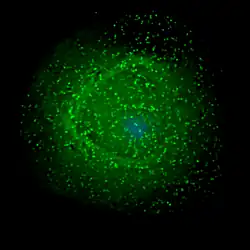

Scanning electron micrograph of HIV-1 (in green) budding from cultured lymphocyte. Multiple round bumps on cell surface represent sites of assembly and budding of virions. | |